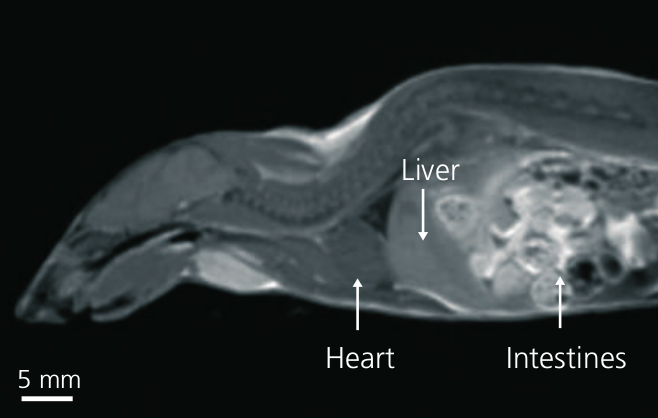

In der Magnetresonanztomographie wird das Gewebe eines Probanden mittels starker Magnetfelder magnetisiert und die resultierenden Signale mit Hilfe von Spulen gemessen. Die gemessenen elektrischen Ströme sind als Rohdaten nicht direkt interpretierbar und müssen mittels mathematischer Methoden rekonstruiert werden. Innerhalb dieses Projekts soll unter anderem für ein existierendes Kleintier-PET/MR-Gerät Methoden und Algorithmen entwickelt bzw. implementiert werden um MRT-Daten zu rekonstruieren (siehe Abbildung, Quelle: Mediso). Das System besteht aus einem 1 Tesla Permanent-Magnet-MRT in Kombination mit einem hochauflösenden PET-System.

In der Magnetresonanztomographie wird das Gewebe eines Probanden mittels starker Magnetfelder magnetisiert und die resultierenden Signale mit Hilfe von Spulen gemessen. Die gemessenen elektrischen Ströme sind als Rohdaten nicht direkt interpretierbar und müssen mittels mathematischer Methoden rekonstruiert werden. Innerhalb dieses Projekts soll unter anderem für ein existierendes Kleintier-PET/MR-Gerät Methoden und Algorithmen entwickelt bzw. implementiert werden um MRT-Daten zu rekonstruieren (siehe Abbildung, Quelle: Mediso). Das System besteht aus einem 1 Tesla Permanent-Magnet-MRT in Kombination mit einem hochauflösenden PET-System.